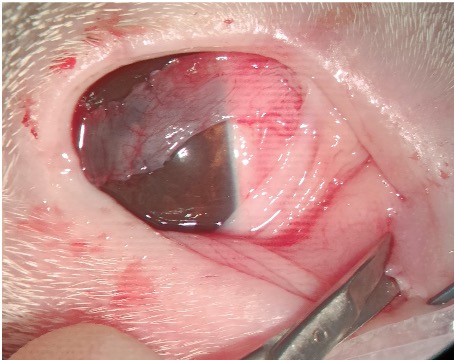

A surgical technique described by Allgoewer (2024), which is also the author’s approach, allows for the removal of a greater length of both the upper and lower eyelids, resulting in a greater reduction of the palpebral fissure. This can be particularly beneficial for patients who require it. The length of the eyelid to be removed can be measured with a Schirmer tear test paper strip or callipers (Figure 2A). Increased visualisation of the canaliculi can be achieved using a Nettleship dilator if necessary (Figure 2B). Both the upper and lower puncta are incised with surgical scissors (Figure 2C), and the canaliculi are opened from the puncta down to the medial fornix.

The nictitans membrane is then exposed using von Graefe forceps or mosquito forceps, and the caruncle is excised (identified as pigmented or non-pigmented conjunctiva, sometimes with hair follicles in the medial rostral fornix). Upper and lower free eyelid margin incisions are made medially at a depth of 3 to 4mm (Figure 2D). These incisions are then extended towards the medial canthus, parallel to the eyelid margins, until they meet at the medial canthal skin, beyond the medial canthus. The distance from the incisions at the free eyelid margin to the medial canthus depends on the total initial eyelid length and the desired final size of the palpebral fissure, which is usually set at 20mm from the “new” medial to lateral canthus (author’s approach to medial canthoplasty). The medial canthal skin is released by cutting the medial canthal ligament, which can be identified at the medial canthus, extending from the medial orbital rim rostrolaterally to the orbicularis oculi muscle beneath the medial canthal skin.

The surgical wound is then closed in two layers. The tarsal suture brings together the “tarsal” plates (deeper layer) of both eyelid margins using a far-near-across-near-far loop technique. This is followed by suturing the subconjunctival layers with 6-0 absorbable suture material using a simple interrupted vertical U suture or a continuous suture pattern. A figure-of-eight suture, bringing together the free eyelid margins, is performed by entering the skin of one eyelid approximately 2mm from the eyelid margin and 1mm from the wound, directed obliquely to the opposite side of the surgical wound.

The needle then enters the contralateral eyelid wound and exits approximately two meibomian gland openings away from the wound margin. This movement is then repeated in reverse on the other side of the wound, entering approximately two meibomian gland openings from the wound margin and directed obliquely to the opposite side, exiting through the eyelid skin 2mm from the free margin and 1mm from the wound margin (Figure 3). All entry and exit points must be equidistant from the wound margins and symmetrical on both sides of the wound. The remainder of the skin incision (involving the skin and orbicularis muscle) is sutured with 6-0 absorbable or non-absorbable suture material using a simple interrupted pattern until the wound is fully closed.